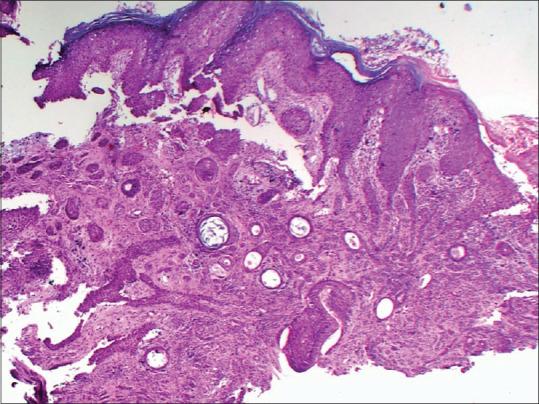

Nodulo-Ulcerative Plaque Over the Vertex of Scalp.

Indian Dermatol Online J. 2023 Feb 23;14(2):292-293. doi: 10.4103/idoj.idoj_240_22. eCollection 2023 Mar-Apr.